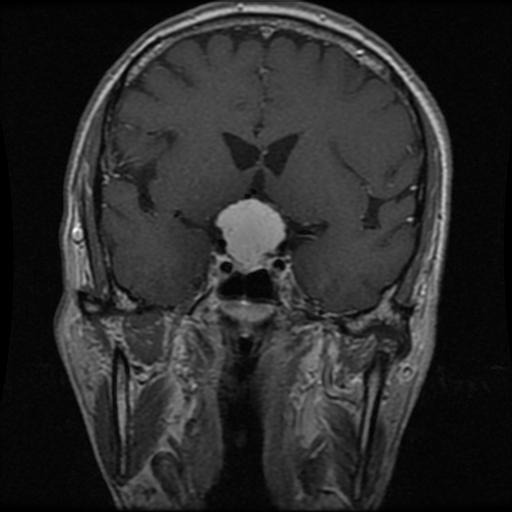

Meningioma

Meningioma

Meningioma

Meningioma